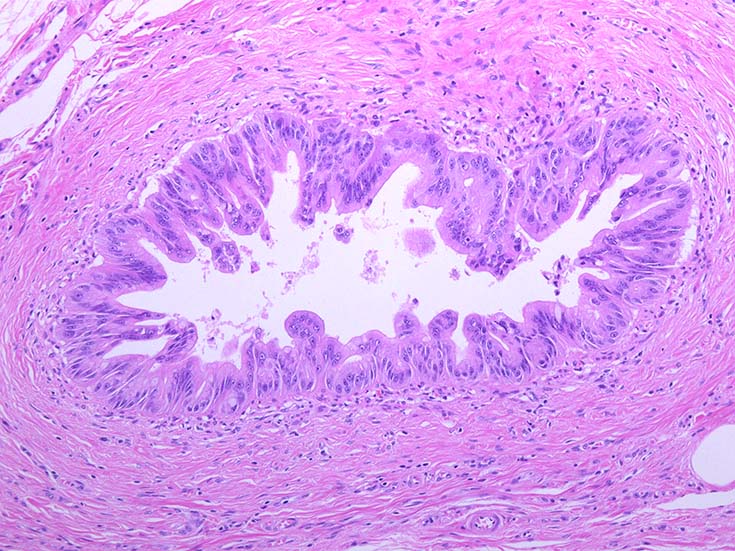

膵上皮内腫瘍性病変 pancreatic intraductal neoplasm(PanIN)*16

Low-grade PanINとhigh-grade PanINの分類

high-grade PanIN

PanINの図譜はJohns Hopkins The Sol Goldman Pancreatic Cancer Research CenterのHome page*19から引用.